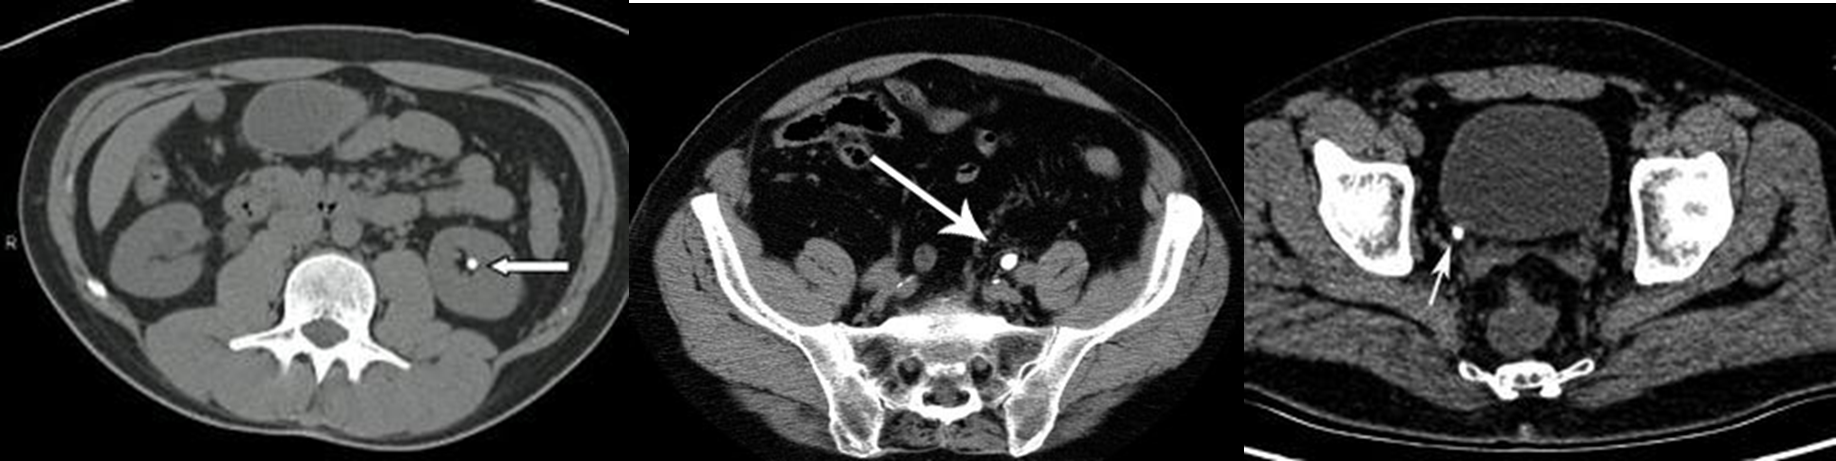

Spiral CT without contrast is the investigation of choice for detection of radiolucent stone specially in ureters.

- Calculus size , location, density , and degree of obstruction

- Hydronephrosis and/or hydroureter

Abdominal CT with IV contrast (venous phase), coronal section

Hyperdense calculi located in the proximal third of the left ureter. As a result, the proximal ureter and the renal pelvis are dilated.